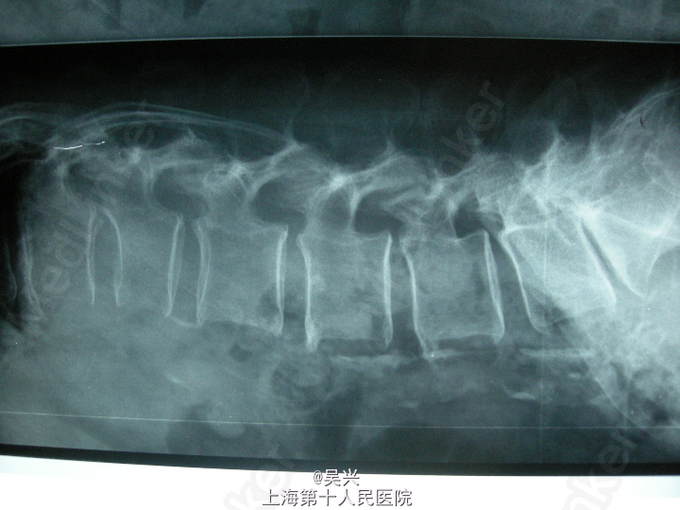

查体:L1棘突压痛,椎体叩击征(+),腰椎活动受限 辅查:X线、MRI片示L1椎体新鲜压缩性骨折

诊断:L1椎体压缩性骨折 处理:入院第二天局麻下行L1压缩性骨折椎体后凸成形术(PKP术)。